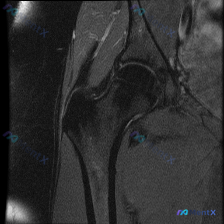

看到一个很有启发的膝关节MRI读片病例,整理了分析思路分享给大家。 病例影像基础信息 这是一幅膝关节矢状位T2加权MRI影像,层面显示髌骨、股骨远端、胫骨近端、髌腱和Hoffa脂肪垫结构,属于膝关节前方矢状面。 影像学异常发现 整理所有客观异常如下: 1. 骨性结构:股骨远端关节软骨下区域可见局灶性...

读片病例整理:膝关节MRI发现软骨异常,分享一下我的分析思路 病例影像基本信息 这是一张膝关节矢状位脂肪抑制T2/PD加权MRI图像,核心观察目标是软骨异常,具体影像发现如下: 1. 骨髓信号异常:股骨远端髁部可见边界模糊的片状高信号,符合骨髓水肿表现;关节面下可见局灶异常高信号,提示软骨下骨损伤或...